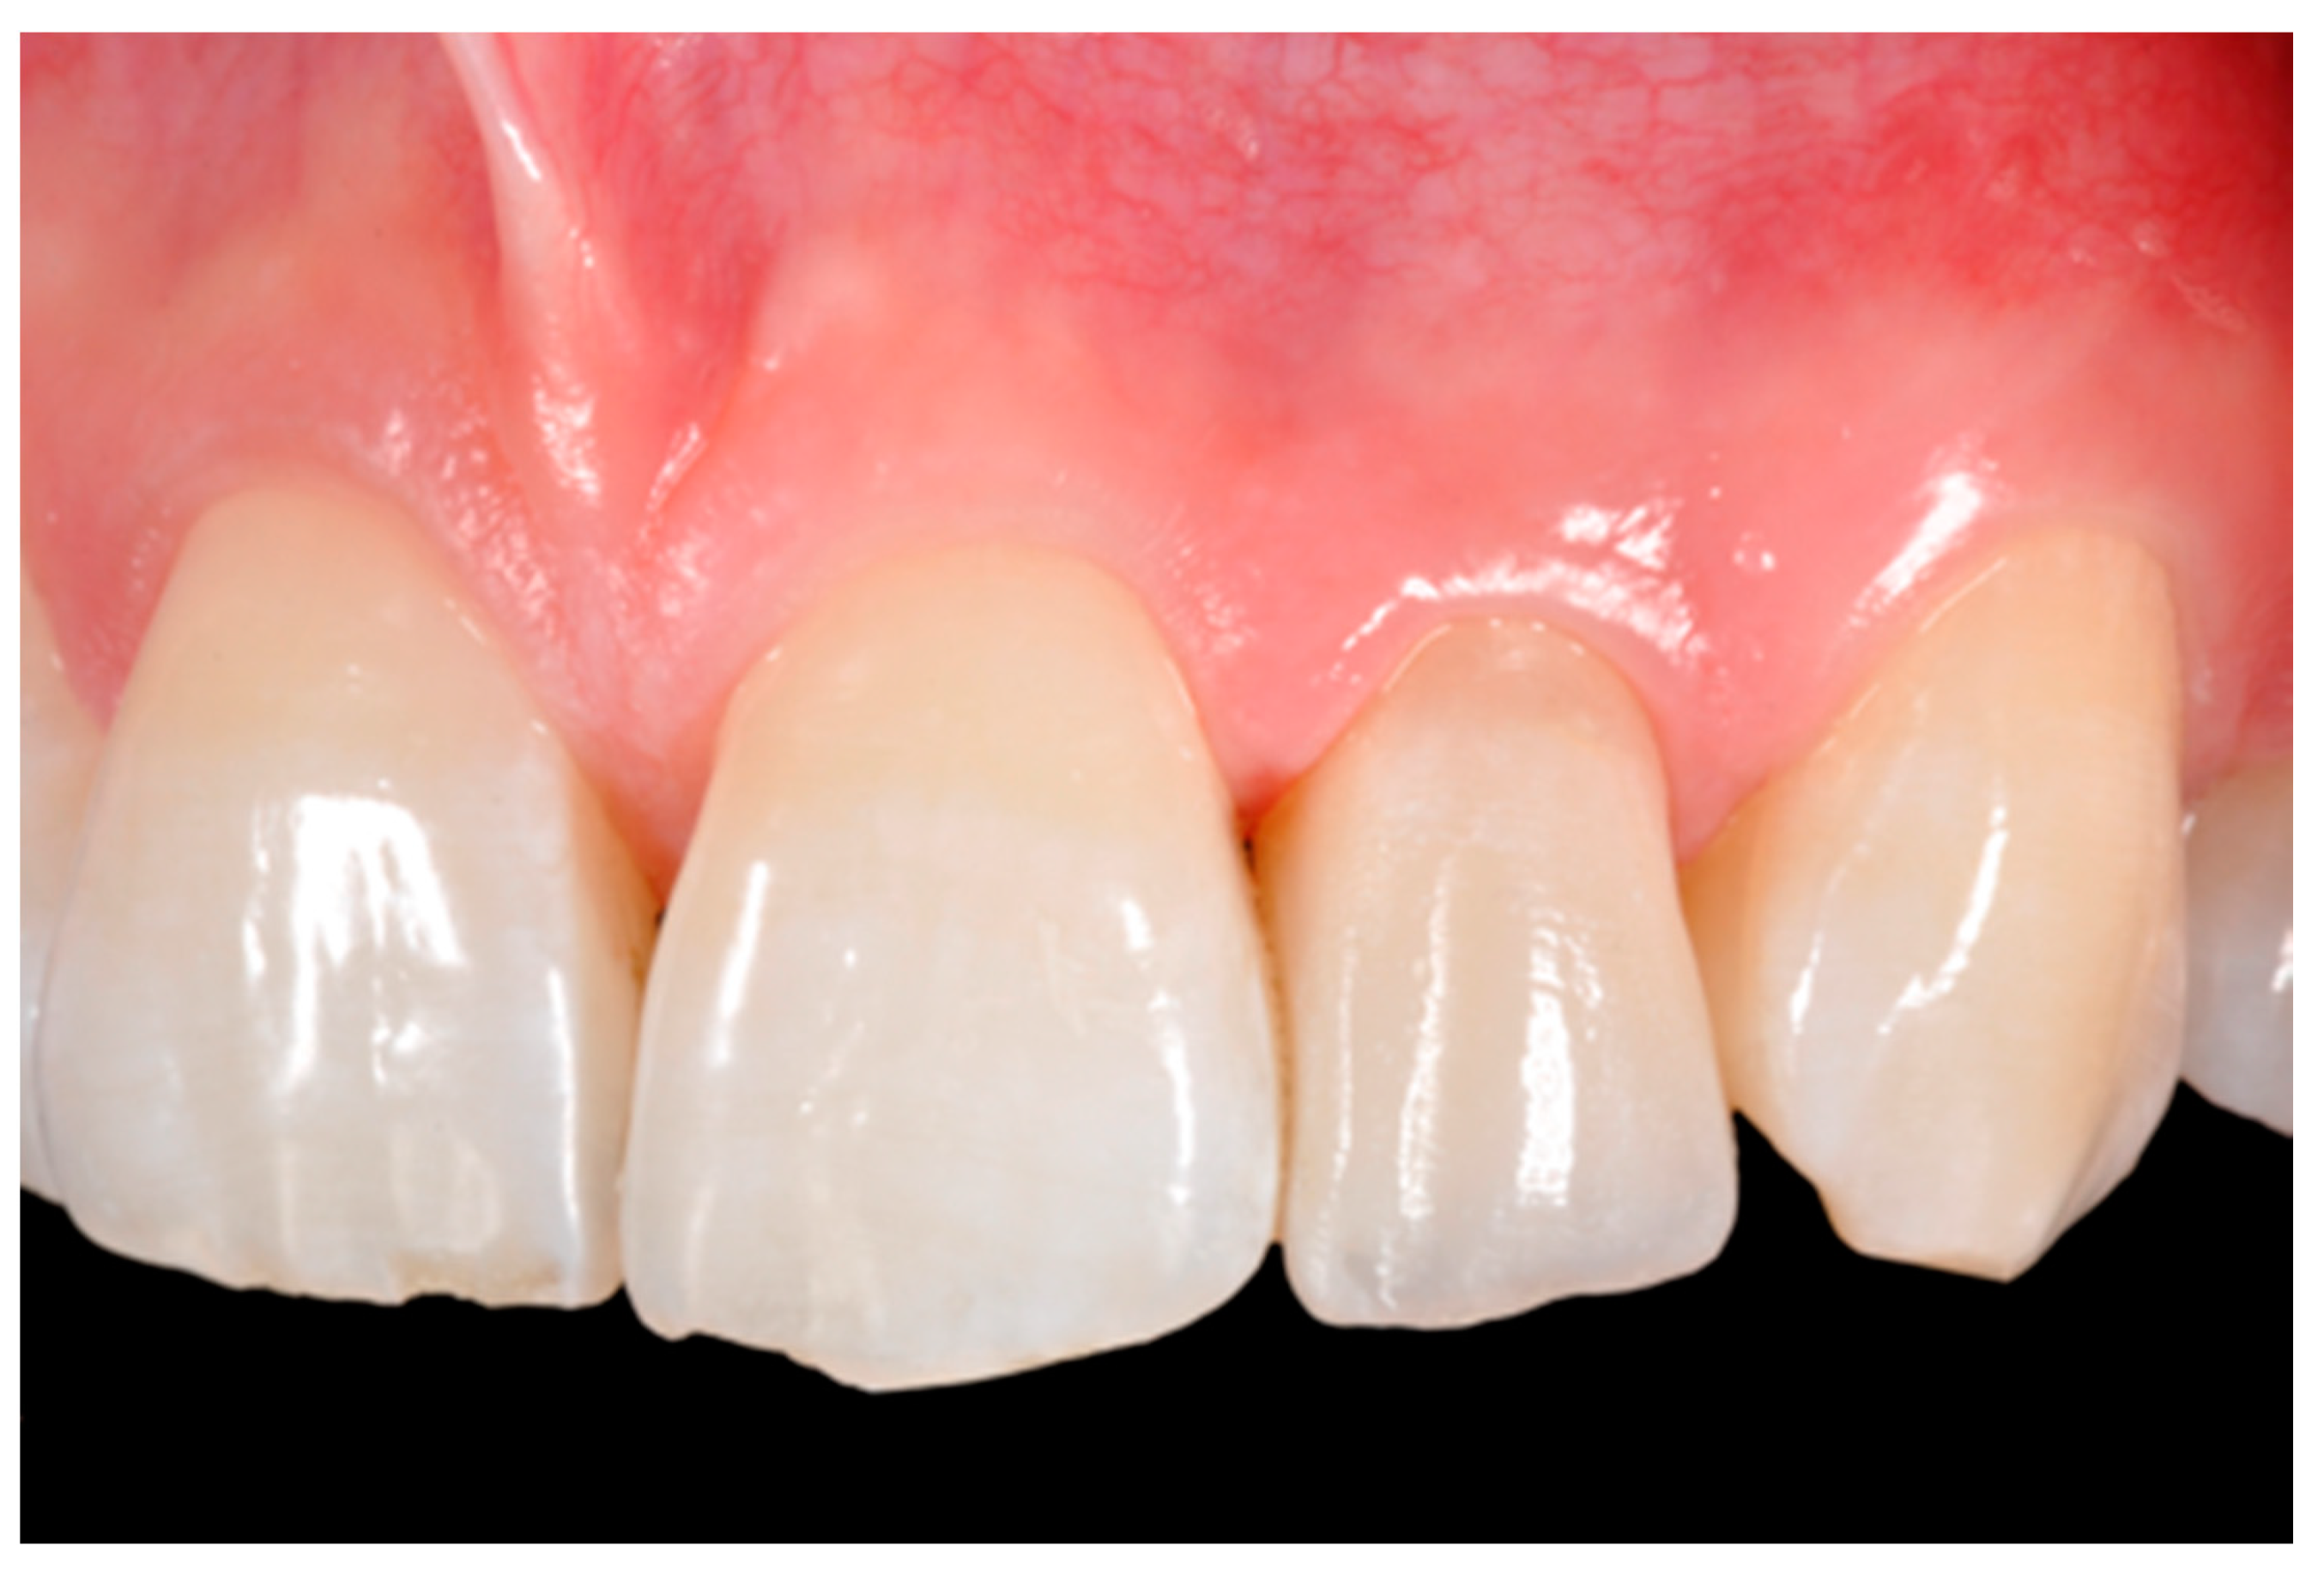

Finishing and polishing procedures were performed with a diamond bur (WL 268 014 Horico, Berlin, Germany), silicone points (Identoflex, Kerr, Bioggio, Switzerland) brushes (Jiffy Goat Air Brushes, Ultradent Products, South Jordan, UT, USA), and diamond pastes (Diamond Polish Mint, Ultradent Products, South Jordan, UT, USA) (Figure 13 and Figure 14). Satisfactory clinical and radiographic outcome was considered satisfactory at 3-months, 1-year, and 5-years post-operative (Figure 15, Figure 16, Figure 17, Figure 18 and Figure 19).

Figure 18.

Five years post-operative.